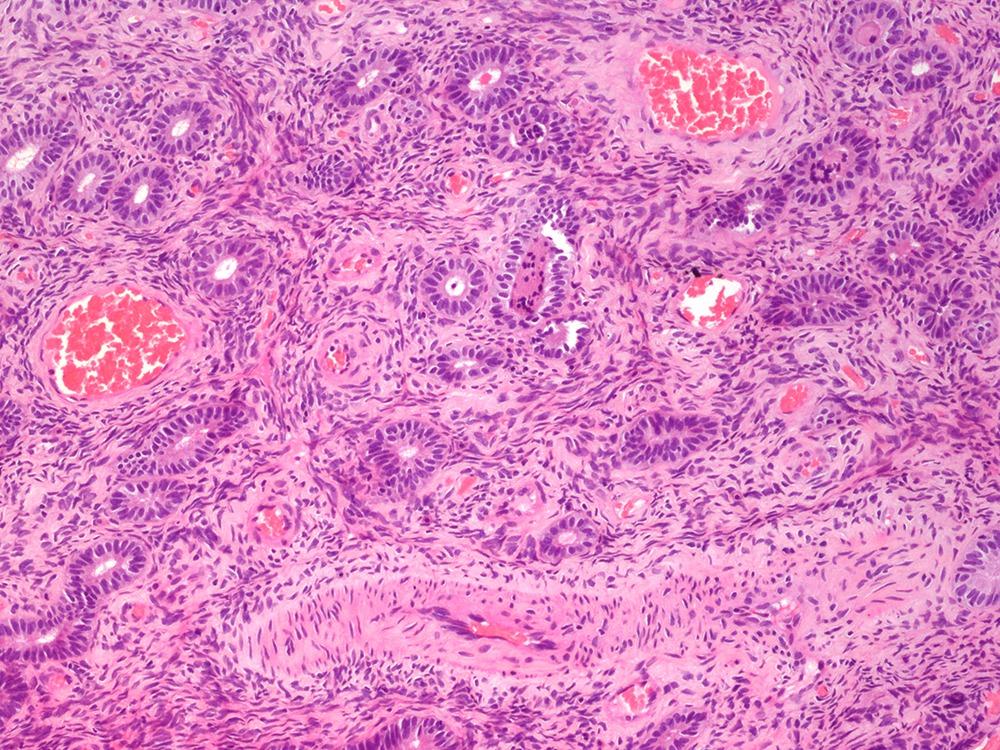

✅ Endometrial atypical hyperplasia / EIN 🎯

• Defined as a geographical lesion where the glandular volume exceeds the stromal volume.

• Shows significant cytological atypia (loss of polarity, rounded nuclei) distinct from background glands.

• It is a clonal proliferation and a direct precursor to low-grade endometrioid adenocarcinoma.

• Often associated with loss of PTEN or PAX2 expression.

❌ Endometrial hyperplasia without atypia:

• This represents a field effect of branched or dilated glands across the whole specimen.

• Crucially, it lacks the localized, geographical expansion seen in atypical hyperplasia.

• The nuclei remain Cigar-shaped and pseudostratified, lacking the rounded, pleomorphic look of EIN.

#PathQuiz 🔬

A) Hyperplasia without atypia

B) Hyperplasia with atypia

C) Endometrial polyp

D) Atypical polypoid adenomyoma

#Pathology #GYNPath #Endometrium

Clue in caption 🧐